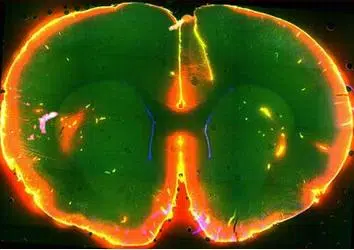

Scientists watched dye flow through the brain of a sleeping mouse. Photo courtesy of Nedergaard Lab, University of Rochester Medical Center)

Initially the researchers studied the system by injecting dye into the cerebrospinal fluid of mice and watching it flow through their brains while simultaneously monitoring electrical brain activity.

The dye flowed rapidly when the mice were unconscious, either asleep or anesthetized. In contrast, the dye barely flowed when the same mice were awake.